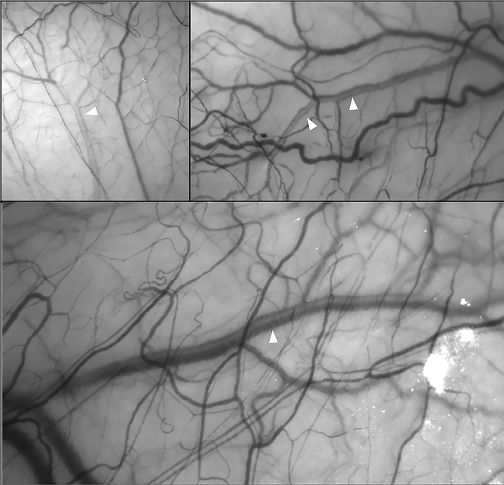

Recently, several non-invasive in-vivo methods have been introduced to measure the episcleral venous outflow. One method is hemoglobin video imaging which assesses the laminar flow in the episcleral veins (i.e., the separation between blood and aqueous within the veins). An interference filter is used and the eye is exposed to a light with a wave length corresponding to the hemoglobin absorption spectrum. The aqueous appears clear since it is devoid of hemoglobin, while the blood appear darker (Figure 2).[14]

Another non-invasive method is erythrocyte-mediated angiography. This technique is based on injecting autologous, indocyanine green–labelled red blood cells into the individual and then direct visualization of these erythrocytes using scanning laser ophthalmoscopy. This allows for accurate quantification of the episcleral blood flow.[15]

Topical ripasudil is another rho-kinase inhibitor that is approved in Japan and Korea. A prospective study by Suzuki and colleagues[22] investigated its effect on aqueous outflow in episcleral venous vasculature compared to latanoprost. The study included 16 healthy, non-glaucomatous eyes. They used hemoglobin video imaging to evaluate the changes in the aqueous column before and after topical ripasudil. They reported a significant increase in the aqueous column width eight hours after the use of topical ripasudil, suggesting enhancement of episcleral venous outflow.

Surgical therapy should be considered if patients are refractory to medical therapy. The aim should be to bypass the trabecular outflow, therefore selective laser trabeculoplasty (SLT) and micro-pulse laser trabeculoplasty (MLT) has not been classically recommended[8]. However, a recent study by Khatib and colleagues evaluated episcleral venous outflow in eight eyes who had undergone SLT. Using hemoglobin video imaging, they demonstrated a significant increase in the aqueous column in the episcleral vasculature following SLT.[14] Several studies are currently conducted to evaluate the episcleral venous outflow before and after various glaucoma procedures using erythrocyte-mediated angiography.[18]